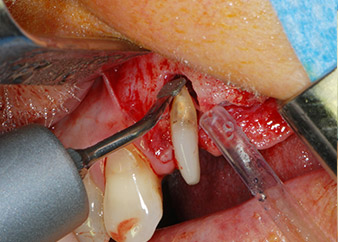

Преди поставянето на импланта, инфектираната тъкан е отстранена от алвеоларната кост в имплантното ложе и около зъба-абатмънт с накрайник, проектиран за оформяне на костта и събиране на костни блокове (Piezomed, накрайник B5) (Фиг. 6 и 7).

Имплантологичното ложе е подготвено в позиции 25 и 26 с ротиращи инструменти, използвайки обратен наконечник 20:1 с усъвършенстван и мощен имплантологичен мотор (Implantmed, W&H) (Фиг. 8).

Следващата препарация близо до синуса отново е извършена с пиезохирургичен накрайник (Piezomed, накрайник S2).